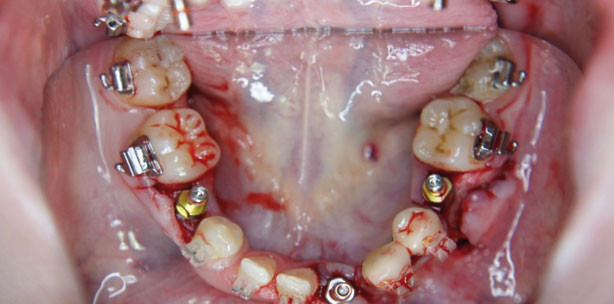

Nach der Erstvorstellung im April 2007 und entsprechender Therapieabsprache mit der Kieferorthopädin sowie erfolgreicher implantologischer Voruntersuchung anhand von Modellen (OPG, Wax-up und Röntgen­schablone) wurden im Dezember 2007 die Milchzähne 55, 62, 64, 65, 75, 73, 83, 84, 85 extrahiert. Die Patientin war zu diesem Zeitpunkt 17 Jahre alt. Zum gleichen operativen Eingriff wurden zwei Implantate in Regio 43 und 44 mit lateraler Augmentation gesetzt, wofür Bio-Oss® und Bio-Gide® (Geistlich) verwendet wurde und welche mit drei Nähten in drei Schichten verschlossen wurde. In Regio 42 erfolgte ein Bone Splitting mittels Piezochirurgie und Meißel. Anschließend wurde der entstandene Zwischenraum mit Bio-Oss® aufgefüllt und mit ­einer Bio-Gide® abgedeckt. Auch hierfür verlief die ­Abdichtung in zwei Schichten. Nach einer Einheilphase von vier Monaten konnten im April 2008 die Implantate 43 und 44 geöffnet, die Pfosten eingeschraubt und die entsprechende Implantatabformung für den therapeutisch-implantologischen Kronenblock angefertigt werden. Dieser stahlgestützte Kronenblock konnte problemlos mit TempBond eingesetzt werden. Anschließend folgte die Versorgung mit einer festsitzenden kieferorthopädischen Apparatur im Ober- und Unterkiefer durch die Kieferorthopädin, wobei die Brackets direkt am Kronenblock der Implantate 43 und 44 befestigt werden konnten (Abb. 6). Die kieferorthopädische Behandlung war mit der Ausformung beider Kiefer soweit erfolgreich, dass im ­Februar 2010 die weitere Implantation im Ober- und Unterkiefer geplant und durchgeführt werden konnte. So war die Implantation in Regio 12, 14, 22, 24 und 34, 42, 45 (Abb. 7 bis 9) möglich, wobei im rechten Oberkiefer, speziell am Implantat 14, ein kleiner interner Sinuslift mittels Osteotom notwendig war. Im linken Oberkiefer wurde eine laterale Augmentation mittels Bio-Oss® und Bio-Gide® ausgeführt sowie ein interner Sinuslift und Verschluss mit einer zweischichtigen Naht. Für die provisorische Versorgung wurden anschließend Kunststoffzähne verwendet, die mithilfe der Multibandapparatur befestigt werden konnten. Die Wundheilung verlief problemlos, sodass nach zehn Tagen die Nähte entfernt werden konnten. Nach Ablauf der Einheilphase von drei Monaten erfolgte die Freilegung von 14, 12, 22, 24, 34, 42 und 45. Zur Optimierung der Ästhetik des Weichgewebes wurde mit der Freilegungsoperation in Regio 22 sowie in Regio 42 bis 45 jeweils eine Mukograft-Collagen-Matrix (Geistlich) eingebracht und fixiert. Die Nähte wurden nach zehn Tagen entfernt.